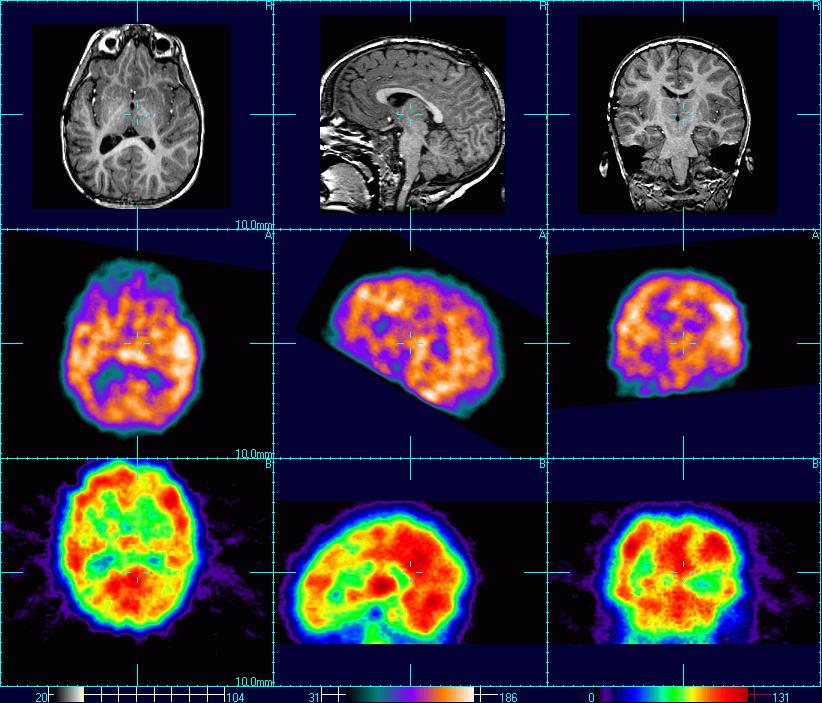

К наступлению осени мне не удалось наладить отношения с женой в плане полноценности нашего общения, поэтому я стал искать, если можно так выразиться, психиатрическое решение своей проблемы. К счастью, среди моих друзей как раз был подходящий специалист. Мой лучший друг среди покеристов, Мэтт Эймен, приходится племянником доктору Дэниэлу Эймену из клиники Amen Clinics. Доктор Эймен широко известен во всём мире и является, возможно, наиболее успешным новатором среди психиатров. Его лечебные заведения соответствуют самым высоким мировым стандартам и оказывают услуги, которые вы не сможете получить почти ни в одной из клиник мира - ОФЭКТ-томографию головного мозга. Для тех, кто далёк от подобного рода исследований, поясню: доктор Эймен использует сканирование мозга для изучения сотрясений в ходе исследований, проводимых Национальной футбольной лигой США. Его работа известна во всём мире. Учитывая всё вышесказанное, а также специфику проблемы человека, который ежедневно мультитейблит по 15 столов, я без тени сомнений решил обратиться в Amen Clinics.

После ответов на многочисленные вопросы, а также после двух сеансов специального сканирования моего головного мозга (первый раз - в расслабленном состоянии, другой - в сконцентрированном) и прохождения нескольких неврологических тестов, я наконец услышал новости. Если коротко, то мне сказали, что в моём мозгу за всё это время развилась определённая последовательность реакций, которая во время концентрации запускала высокопроизводительный аналитический цикл. Этот "цикл" стал настолько скоростным, что теперь стало ясно, как мне удавалось играть в покер на высоком уровне на таком большом количестве столов. Мне сказали, что до тех пор, пока я мог удерживать свой разум в состоянии упомянутого "цикла" - я был бы супер-производительным в своей области. Однако после длительного пребывания в "цикле" мой мозг уже не мог нормально функционировать за его пределами в течение нескольких часов. На деле одним из последствий такого "застревания в цикле" была невозможность нормально общаться с людьми некоторое время после катки, даже если очень сильно этого захочешь.

Но это ещё не всё. Из сканов моего мозга удалось извлечь кое-что ещё более любопытное. Та область моего мозга, которая отвечает за раздражительность и ухудшение настроения, проявляла значительно меньшую активность во время концентрации, чем в расслабленном состоянии. Мне сказали, что это чрезвычайно редкий случай. Я тут же набрал Джареда Тендлера (мой наставник по психологии и мотивации в покере) и поделился с ним этой невероятной новостью. Раньше всё было с точностью до наоборот: я был лёгок на подъём, когда ничем особо не занимался, но становился крайне раздражительным во время покерных сессий. Учитывая, что подход Джареда к преодолению ментальных трудностей разительно отличается от подхода большинства его коллег, ему удалось просто искоренить мои проблемы, которые я испытывал раньше во время игры в покер. Он буквально "перепрошил" мой мозг, сделав из меня хладнокровную машину за покерными столами. Я просто не мог в это поверить!

Если хорошенько подумать, всё это действительно приобретает определённый смысл. С какого перепугу мы решили, что масс-мультитейблинг никак не скажется на здоровье нашего мозга? Когда ещё в истории человечества с людьми происходило хоть что-нибудь подобное? Когда ещё многомиллиардная индустрия поощряла кого-нибудь, кто способен побеждать в 15 видео-играх одновременно? Сколько по времени всё это уже творится? Определённо начало было положено не раньше прошлого века и повсеместного распространения Интернета. Я веду к тому, что все мы своего рода подопытные кролики в этом огромном эксперименте. Для меня его результаты оказались весьма плачевными, и у меня есть сканы собственного мозга, чтобы это доказать.

Если кто-нибудь всё-таки дочитал мой пост до конца - спасибо вам большое. Я буду следить за обсуждением, которое наверняка появится, а также планирую расписать свой опыт подробнее в будущих постах. На данный момент моей целью было поделиться с общественностью своей историей и предупредить вас о том, что рассказали мне врачи. Помните о том, что я сам всё-таки не медик и поэтому всё написанное выше можно воспринимать с определённой долей скепсиса. Если кто-нибудь из вас по прочтении этого поста задумался о своём здоровье, я бы порекомендовал просканировать свой мозг, как это сделал я, потому что данная мера позволит вам узнать о своём мозге то, что обычный психиатр увидеть не в силах.